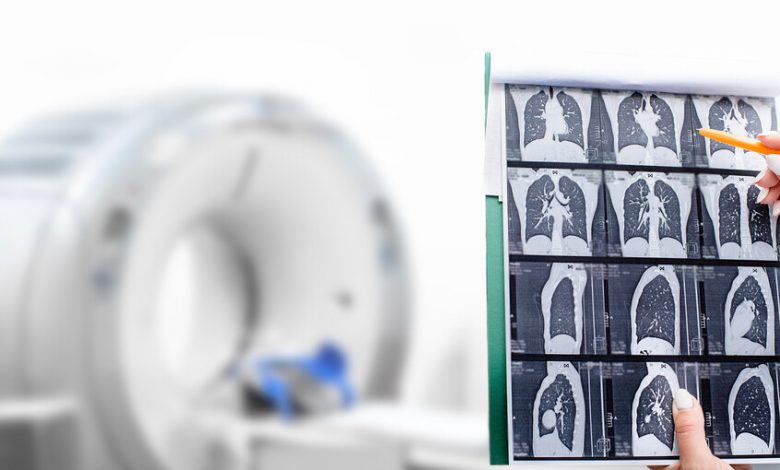

تمكّن فريق بحثي ألماني من كشف آلية جديدة تسهم في فهم سبب عدوانية سرطان الخلايا الصغيرة في الرئة (SCLC)، وهو أحد أكثر أنواع السرطان خطورة وصعوبة في العلاج.

سرطان الرئة ذو الخلايا الصغيرة يُعد من أخطر الأورام، إذ لا يتجاوز معدل البقاء على قيد الحياة لمدة خمس سنوات 5% فقط، رغم استجابته الأولية للعلاج الكيميائي، لأنه غالبا ما يعاود الانتشار بسرعة.

أظهرت الدراسة التي نشرتها مجلة Nature Communications، بقيادة البروفيسورة سيلفيا فون كارستيدت، آلية جديدة تفسر عدوانية هذا النوع من السرطان. هذا النوع، على عكس سرطانات الخلايا الظهارية الأخرى، يُظهر سمات مشابهة للخلايا العصبية، بما في ذلك نقص بروتين “كاسباز-8″، المسؤول عن موت الخلية المبرمج، وهو ضروري لإزالة الخلايا التالفة أو المتحولة.